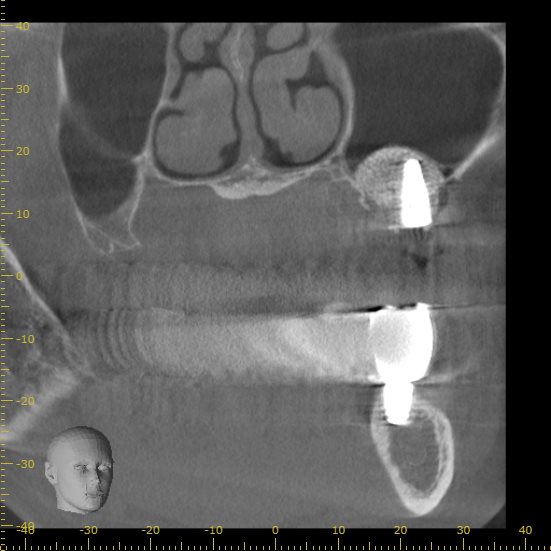

正面から見たCT画像です。

今回の画像をみるとわかりますが、骨が極端に少ない状態です。

正面から見た画像です。

インプラントの半分以上に骨が足りない状態です。

現状の骨の状態でインプラントを行うこと自体が難しいと判断できます。

実際の処置後です。

下の歯と本数を揃えるため、計画を再立案し3本のインプラントを埋入しました。

インプラントの上にドーム状に広がっているのがサイナスリフトを行い填入された人工骨です。